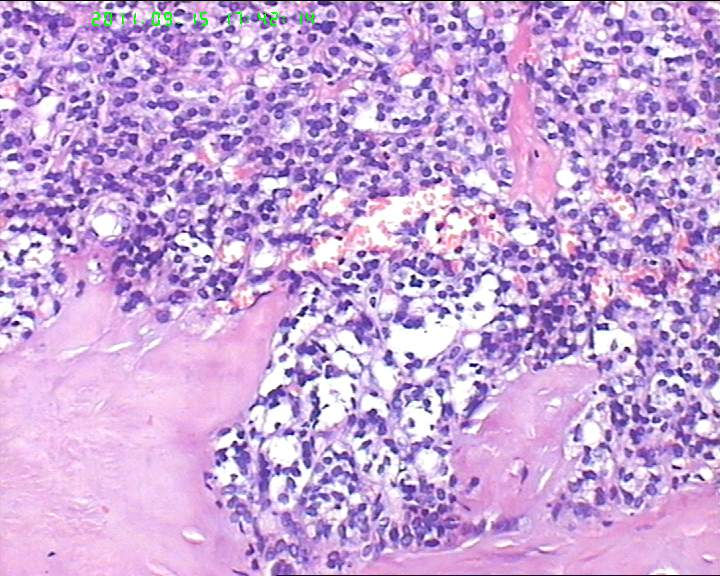

甲状腺右下极一肿物,3*3大小,切面灰红实性质韧,可见部分包膜,一侧可见一空腔,未见内容物。

38岁女性甲状腺,腺瘤?滤泡癌?图1

名称:图1

描述:20110915-1.jpg.jpg

够不够滤泡癌,要找有没有浸润。网友们,这么多图片,有包膜浸润吗(哪几张是包膜)?图12、14又是什么?

同意李老师的观点。该例目前为止无一张图片显示总体包膜情况(有无包膜,是否腺瘤)。建议楼主上传低倍镜图片。